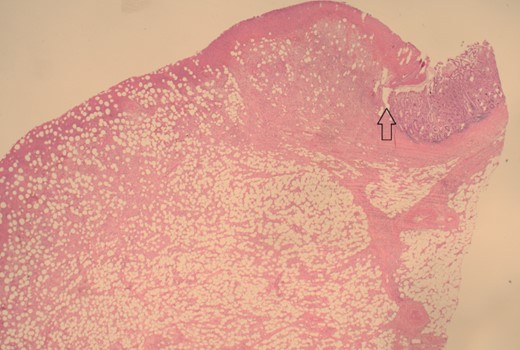

12.5× magnification showing the intact surface small bowel mucosa with the underlying lipoma.

12.5× magnification showing the junction between the ulcerated leading point of the intussusception on the left and the preserved mucosa on the right of the arrow.